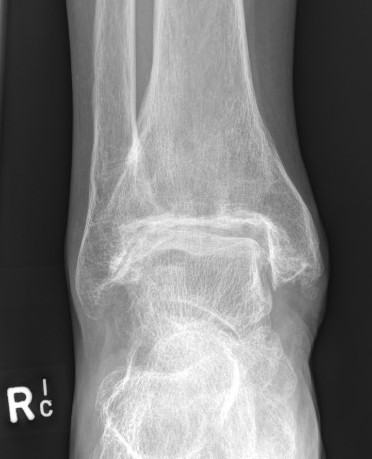

Indication

Malalignment > 15 degrees